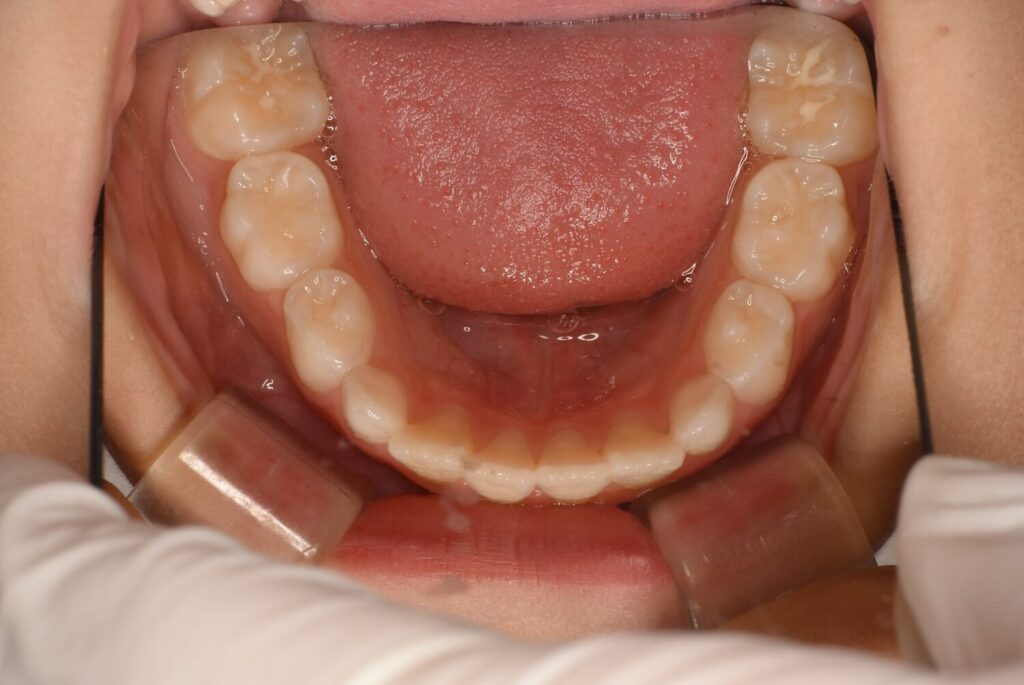

歯が少しずつアーチの方によっています。

ここまでくれば綺麗にアーチの中に入れそうなので装置も外しています。

長く使わないことも併用装置のメリットです。

アクティビティーが終わっても永久歯列になるまでは数ヶ月に一度のご来院をお願いしています。

歯並びも順調に生え変わりましたが、左側の後ろから2番目の歯は少し歪んだ方向から生えてきました。

患者さん自身は今は気になっていないため、一旦治療は終了していますが、希望があればマイオブレース(myobrace)治療にて改善も可能です。